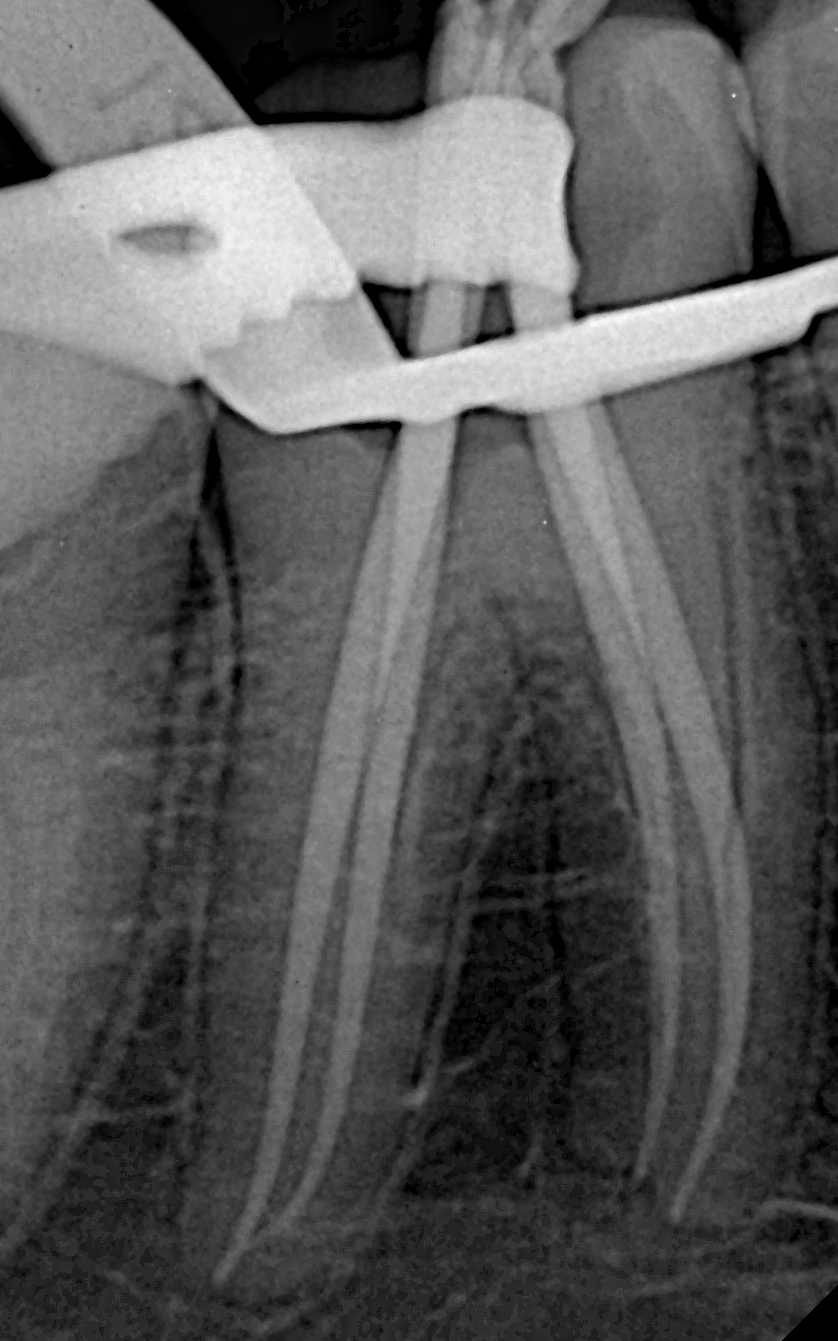

- Manualless Glide Path: The Chameleon 19/02 Rotary File (size 19, taper 0.02) created a smooth glide path in obliterated canals—no manual FILESneeded.

- Canal Shaping with 20/04 File: A seamless transition to the Chameleon 20/04 Rotary File (size 20, taper 0.04) followed. Chemomechanical preparation was done with this file, plus copious irrigation of all canals using 2.5% NaOCl (sodium hypochlorite) for disinfection and debris removal.

- Final Apical Shaping:

- Mesial canals (MB, ML): Chameleon 25/04 Rotary File (size 25, taper 0.04) served as the “Master Apical File.”

- Distal canals (DB, DL): Larger preparation with Chameleon 25/06 Rotary File (size 25, taper 0.06) to accommodate the apical curvature.